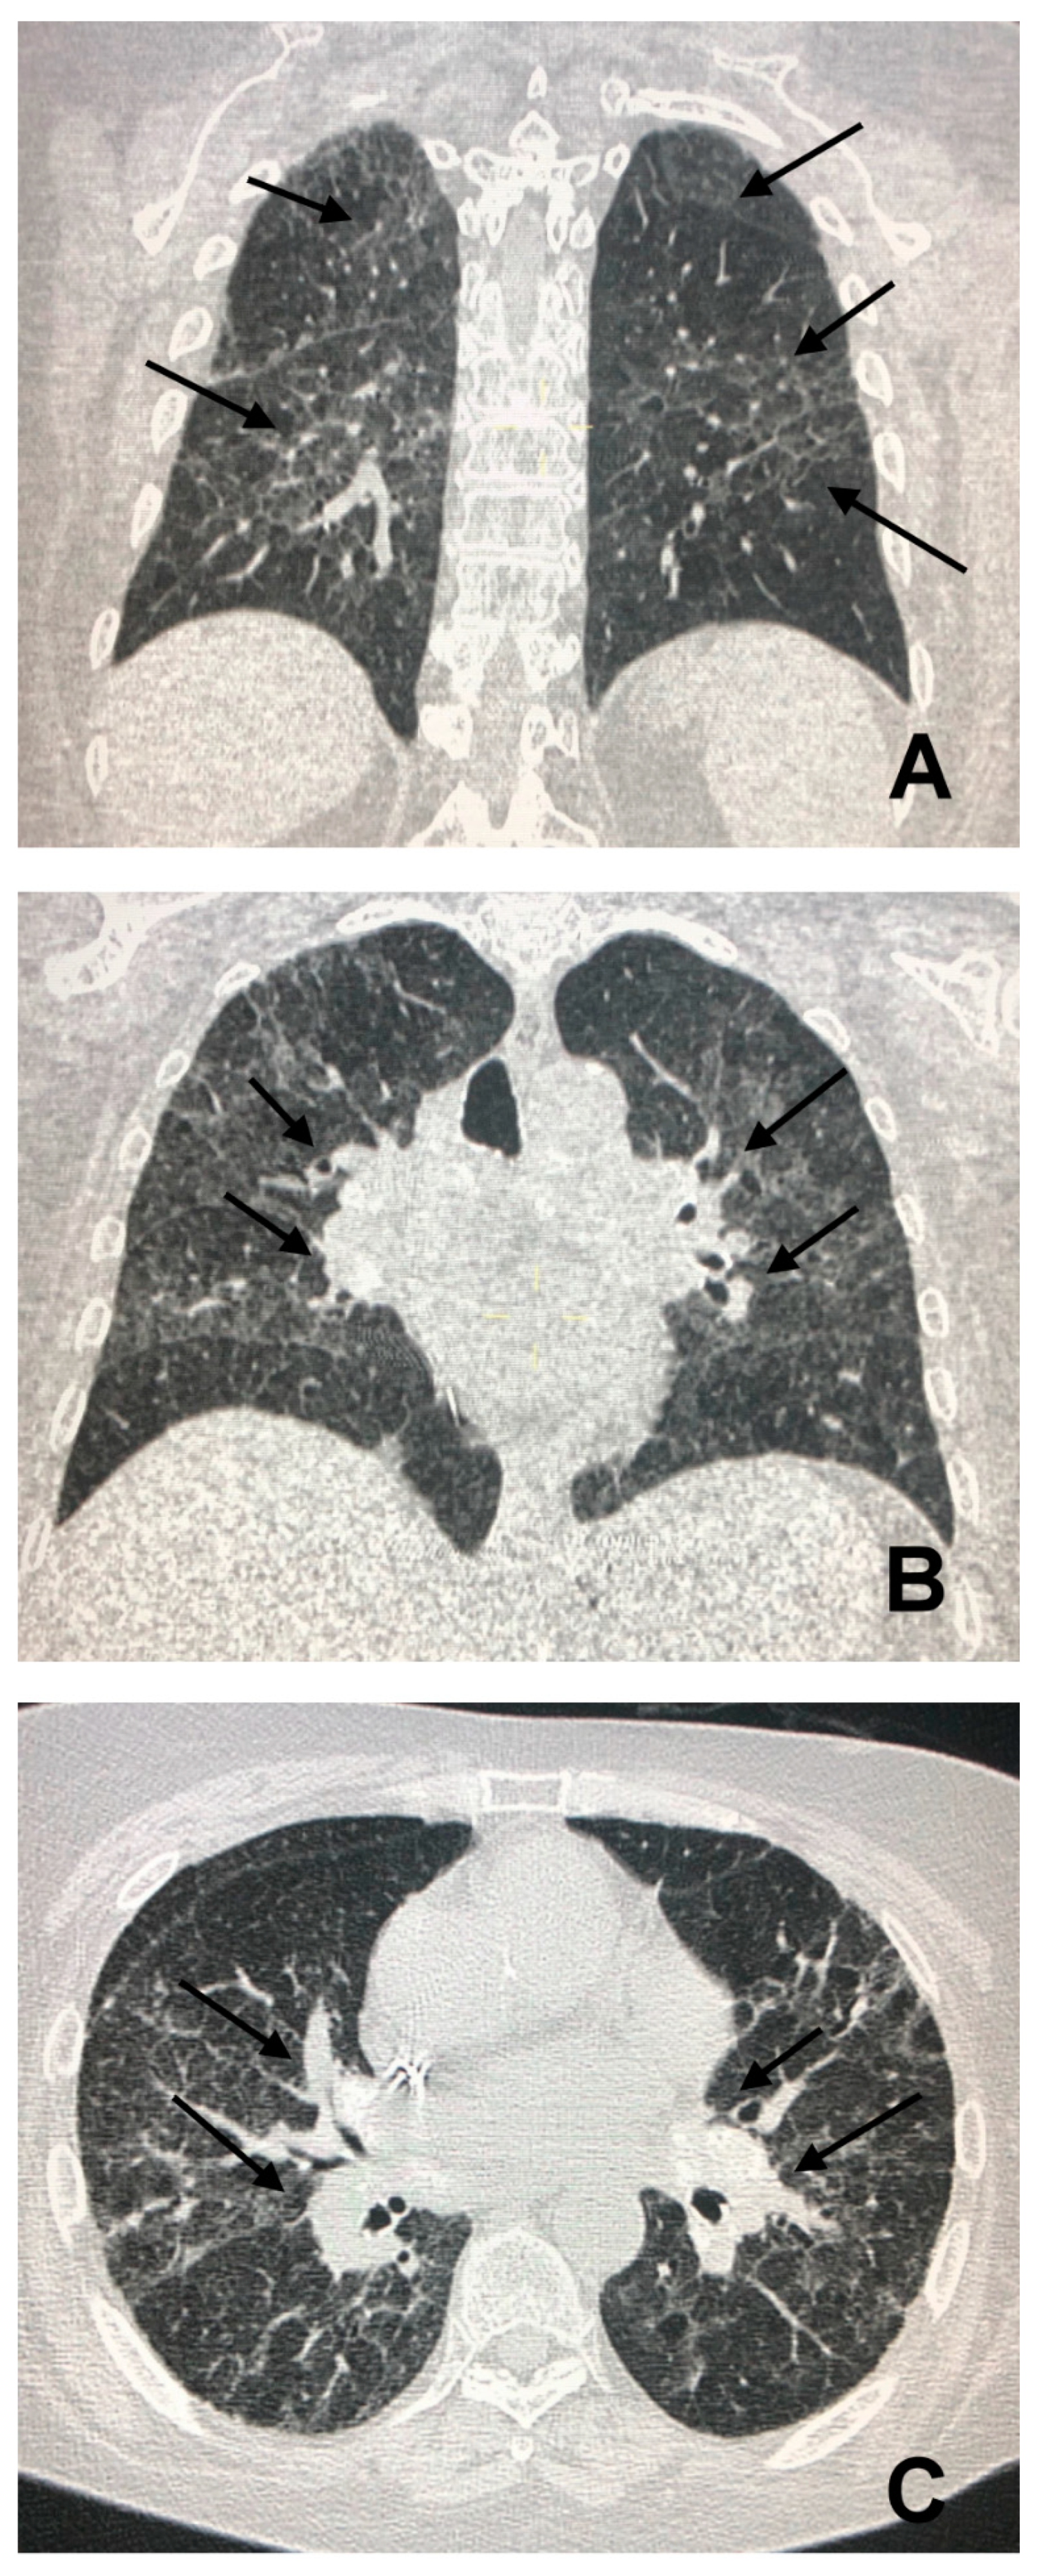

3. CT in Pulmonary Sarcoidosis, Imaging Findings and Classification

4.1. The Involvement of Liver, Spleen and Abdominal Lymph Nodes